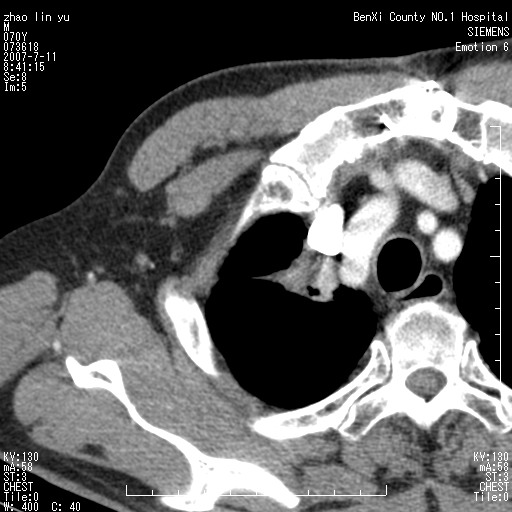

以下是引用王靖旗在2007-7-10 17:12:00的发言:[br] 男、70、咳嗽两个月,半年前换瓣手术,胸片未见异常,于昨天行x片发现右肺上野大片影,行ct扫描,这里是减薄图像,余肺正常。明天晚上会有增强扫描片,到时我会上传。[br][br] 冠状位请大家细看,应该是有意义的,[br][br] 请大家先看平扫发表意见。[br][br]